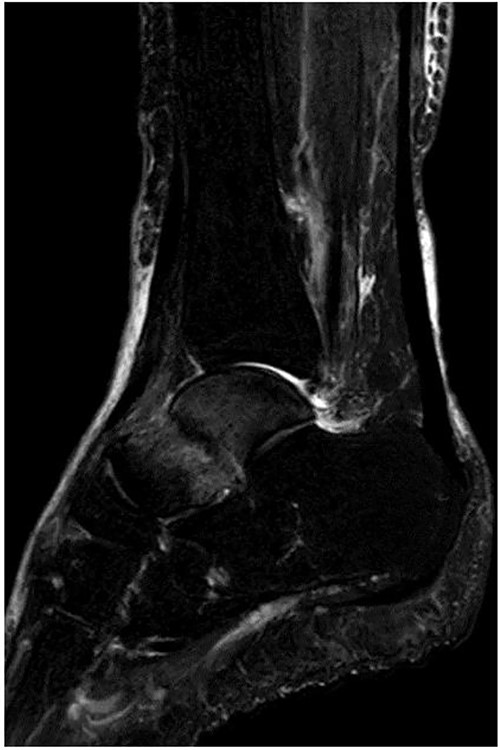

A 76-year-old female, who worked as a cleaner, complained of pain in her right ankle when going downstairs while working. She had medical history of only osteoporosis and had taking daily active vitamin D for >10 years. She was given conservative treatment for 1 month at a local clinic, however, her ankle pain persisted and so she visited our clinic. Physical examinations revealed tenderness and swelling at the anterior aspect of the ankle. Plain radiographs showed no obvious abnormal findings (Fig. 1). Magnetic resonance imaging (MRI) revealed a low signal linear line in the talar neck and a bone marrow edema around the line (Fig. 2). Non-contrast computed tomography (CT) demonstrated an obvious fracture line in the talar neck, however, the bone fragment was not displaced (Fig. 3). Based on medical histories, clinical and radiological findings, we diagnosed her with a fragility fracture of the talar neck associated with osteoporosis. Because the patient was elderly and it was difficult to treat using a prolonged non-weightbearing cast, we applied operative treatment to allow early rehabilitation. The operation was performed under spinal anesthesia in a prone position with an air tourniquet and a fluoroscopy. The posteromedial and posterolateral portals were created according to van Dijk et al. [10]. First, the posterior aspect of the talus was observed using a 4.0-mm diameter 30° arthroscope, and soft tissues around the talus (including synovium and adipose tissues) were removed with a 3.5-mm diameter motorized shaver. After confirming the posterior part of the talar body and the FHL, two 1.6-mm diameter guidewires were parallelly inserted from the posterior part of the talar body to the talar head by hindfoot endoscopy and fluoroscopy (Fig. 4A), and two cannulated 4.5-mm diameter double-threaded screws (Double Thread Screw, Meira, Nagoya, Japan) were inserted through the guidewires (Fig. 4B). The wound was sutured, and the operation was concluded (Fig. 5). Active range of motion exercises were allowed immediately after surgery, and a non-weightbearing short leg splint was worn for 1 week. Partial-weight bearing was permitted at 2 weeks and full-weight bearing was permitted at 4 weeks post-operatively. In addition, daily injections of teriparatide (Forteo, Eli Lilly and Company, Indianapolis, IN, USA) were introduced 2 weeks post-operatively. Eight weeks after the operation, the patient was able to return to work without pain or functional impairment. One year postsurgery, the patient was still working as a cleaner without any symptoms or complications.

MRI revealed a low signal linear line in the talar neck and a bone marrow edema around the line on a fat-suppressed T2-weighted (FS-T2) image.